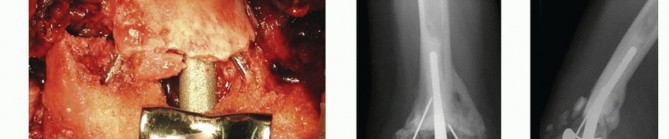

TECH FIG 4 • A. The humeral component entry point, the apex of the olecranon fossa, is identified, and humeral canal preparation is commenced by opening the canal with a bone nibbler or burr.(continued)